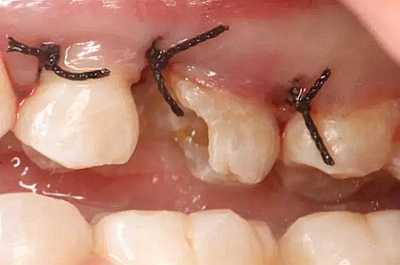

患牙遠中邊緣嵴完整,強度沒有降低,故擬保留遠中邊緣嵴,高嵌體修復。首先去除腐質(zhì)及原墊底材料,流體樹脂+3M Z350XT樹脂墊底。局麻下行冠延長手術。在此需要提及個人的一個觀點。冠延長手術原則上要求3-6個月以上才能永久修復。但是個人喜歡后牙肩臺建立在齦上,所以修復后的修復體邊緣位于牙齦上方1mm,對牙周的愈合影響較?。ㄈ绻麨辇l下邊緣則要慎重),故該患者術中按照齦上邊緣的設計進行冠延長手術。以下為術中:

改良垂直褥式縫合關閉傷口,傷口無明顯滲血,高嵌體預備完畢后,硅橡膠取模,見邊緣清晰。灌注模型,模型上3MZ350XT分層堆塑高嵌體。